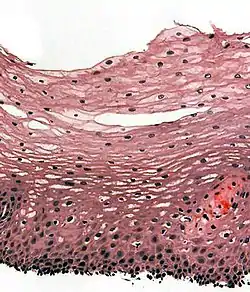

The human esophagus has a mucous membrane consisting of a tough stratified squamous epithelium without keratin, a smooth lamina propria, and a muscularis mucosae.[6] The epithelium of the esophagus has a relatively rapid turnover and serves a protective function against the abrasive effects of food. In many animals, the epithelium contains a layer of keratin, representing a coarser diet.[19] There are two types of glands, with mucus-secreting esophageal glands being found in the submucosa and esophageal cardiac glands, similar to cardiac glands of the stomach, located in the lamina propria and most frequent in the terminal part of the organ.[19][20] The mucus from the glands gives a good protection to the lining.[21] The submucosa also contains the submucosal plexus, a network of nerve cells that is part of the enteric nervous system.[19]

The muscular layer of the esophagus has two types of muscle. The upper third of the esophagus contains striated muscle, the lower third contains smooth muscle, and the middle third contains a mixture of both.[6] Muscle is arranged in two layers: one in which the muscle fibers run longitudinal to the esophagus, and the other in which the fibers encircle the esophagus. These are separated by the myenteric plexus, a tangled network of nerve fibers involved in the secretion of mucus and in peristalsis of the smooth muscle of the esophagus. The outermost layer of the esophagus is the adventitia in most of its length, with the abdominal part being covered in serosa. This makes it distinct from many other structures in the gastrointestinal tract that only have a serosa.[6]